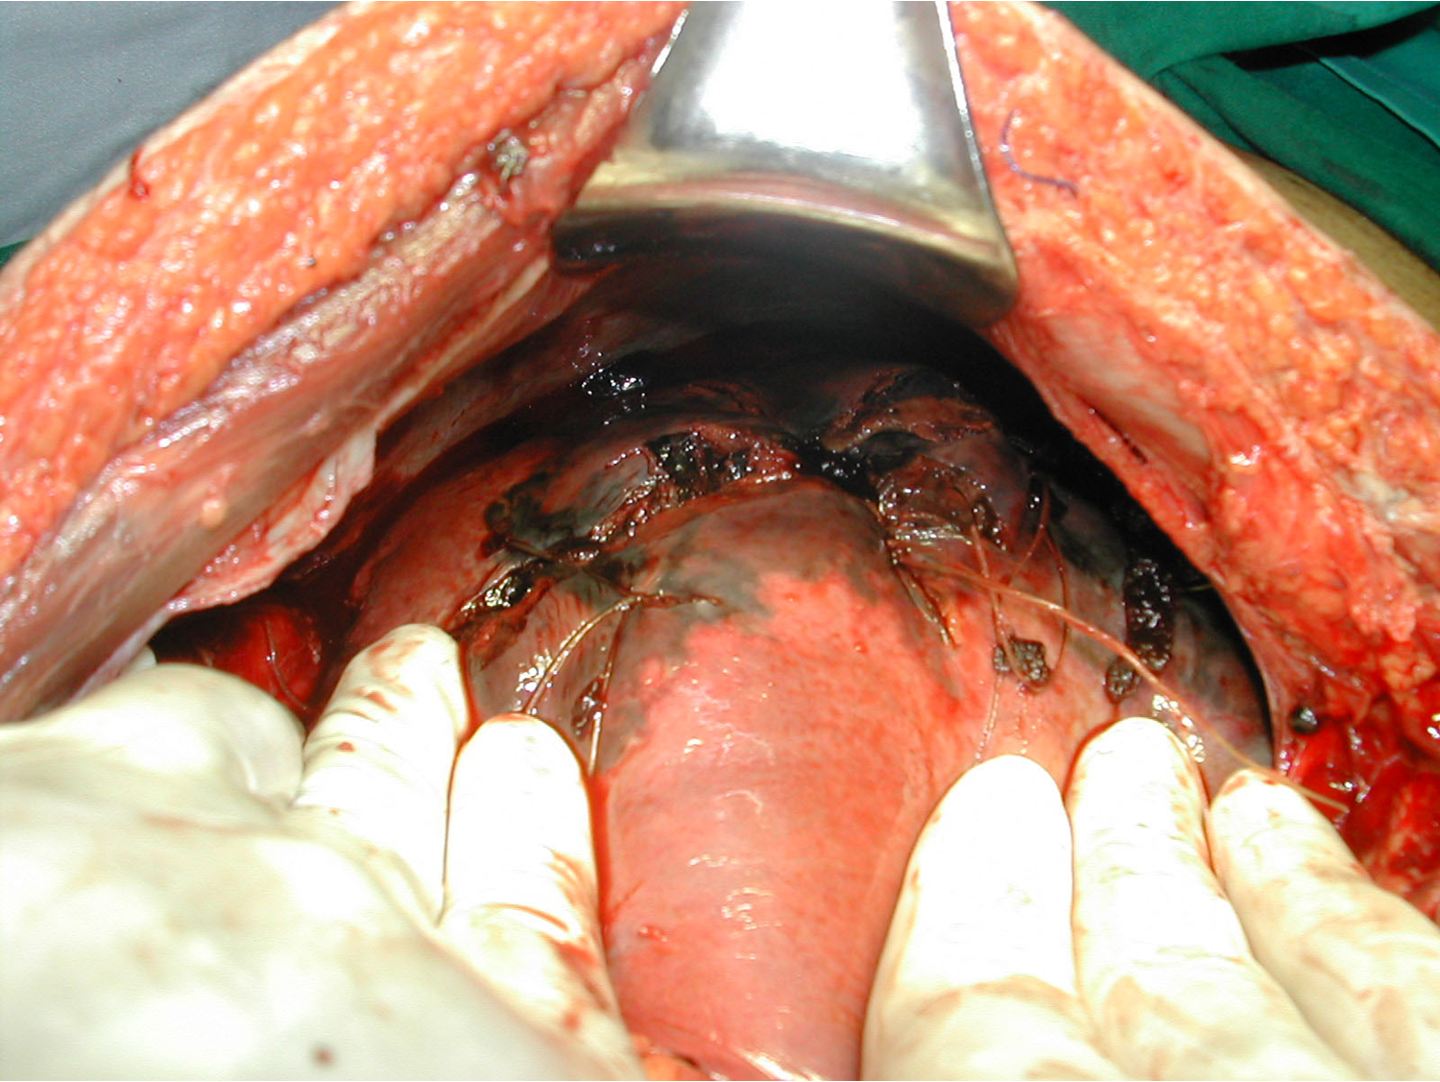

Liver injury-Surgical management

Principles of surgical management:

- control of bleeding,

- removal of devitalized tissue, and

- adequate drainage.

Perihepatic packing- if fail to control bleeding.

-

Packs removed in 48 hours.